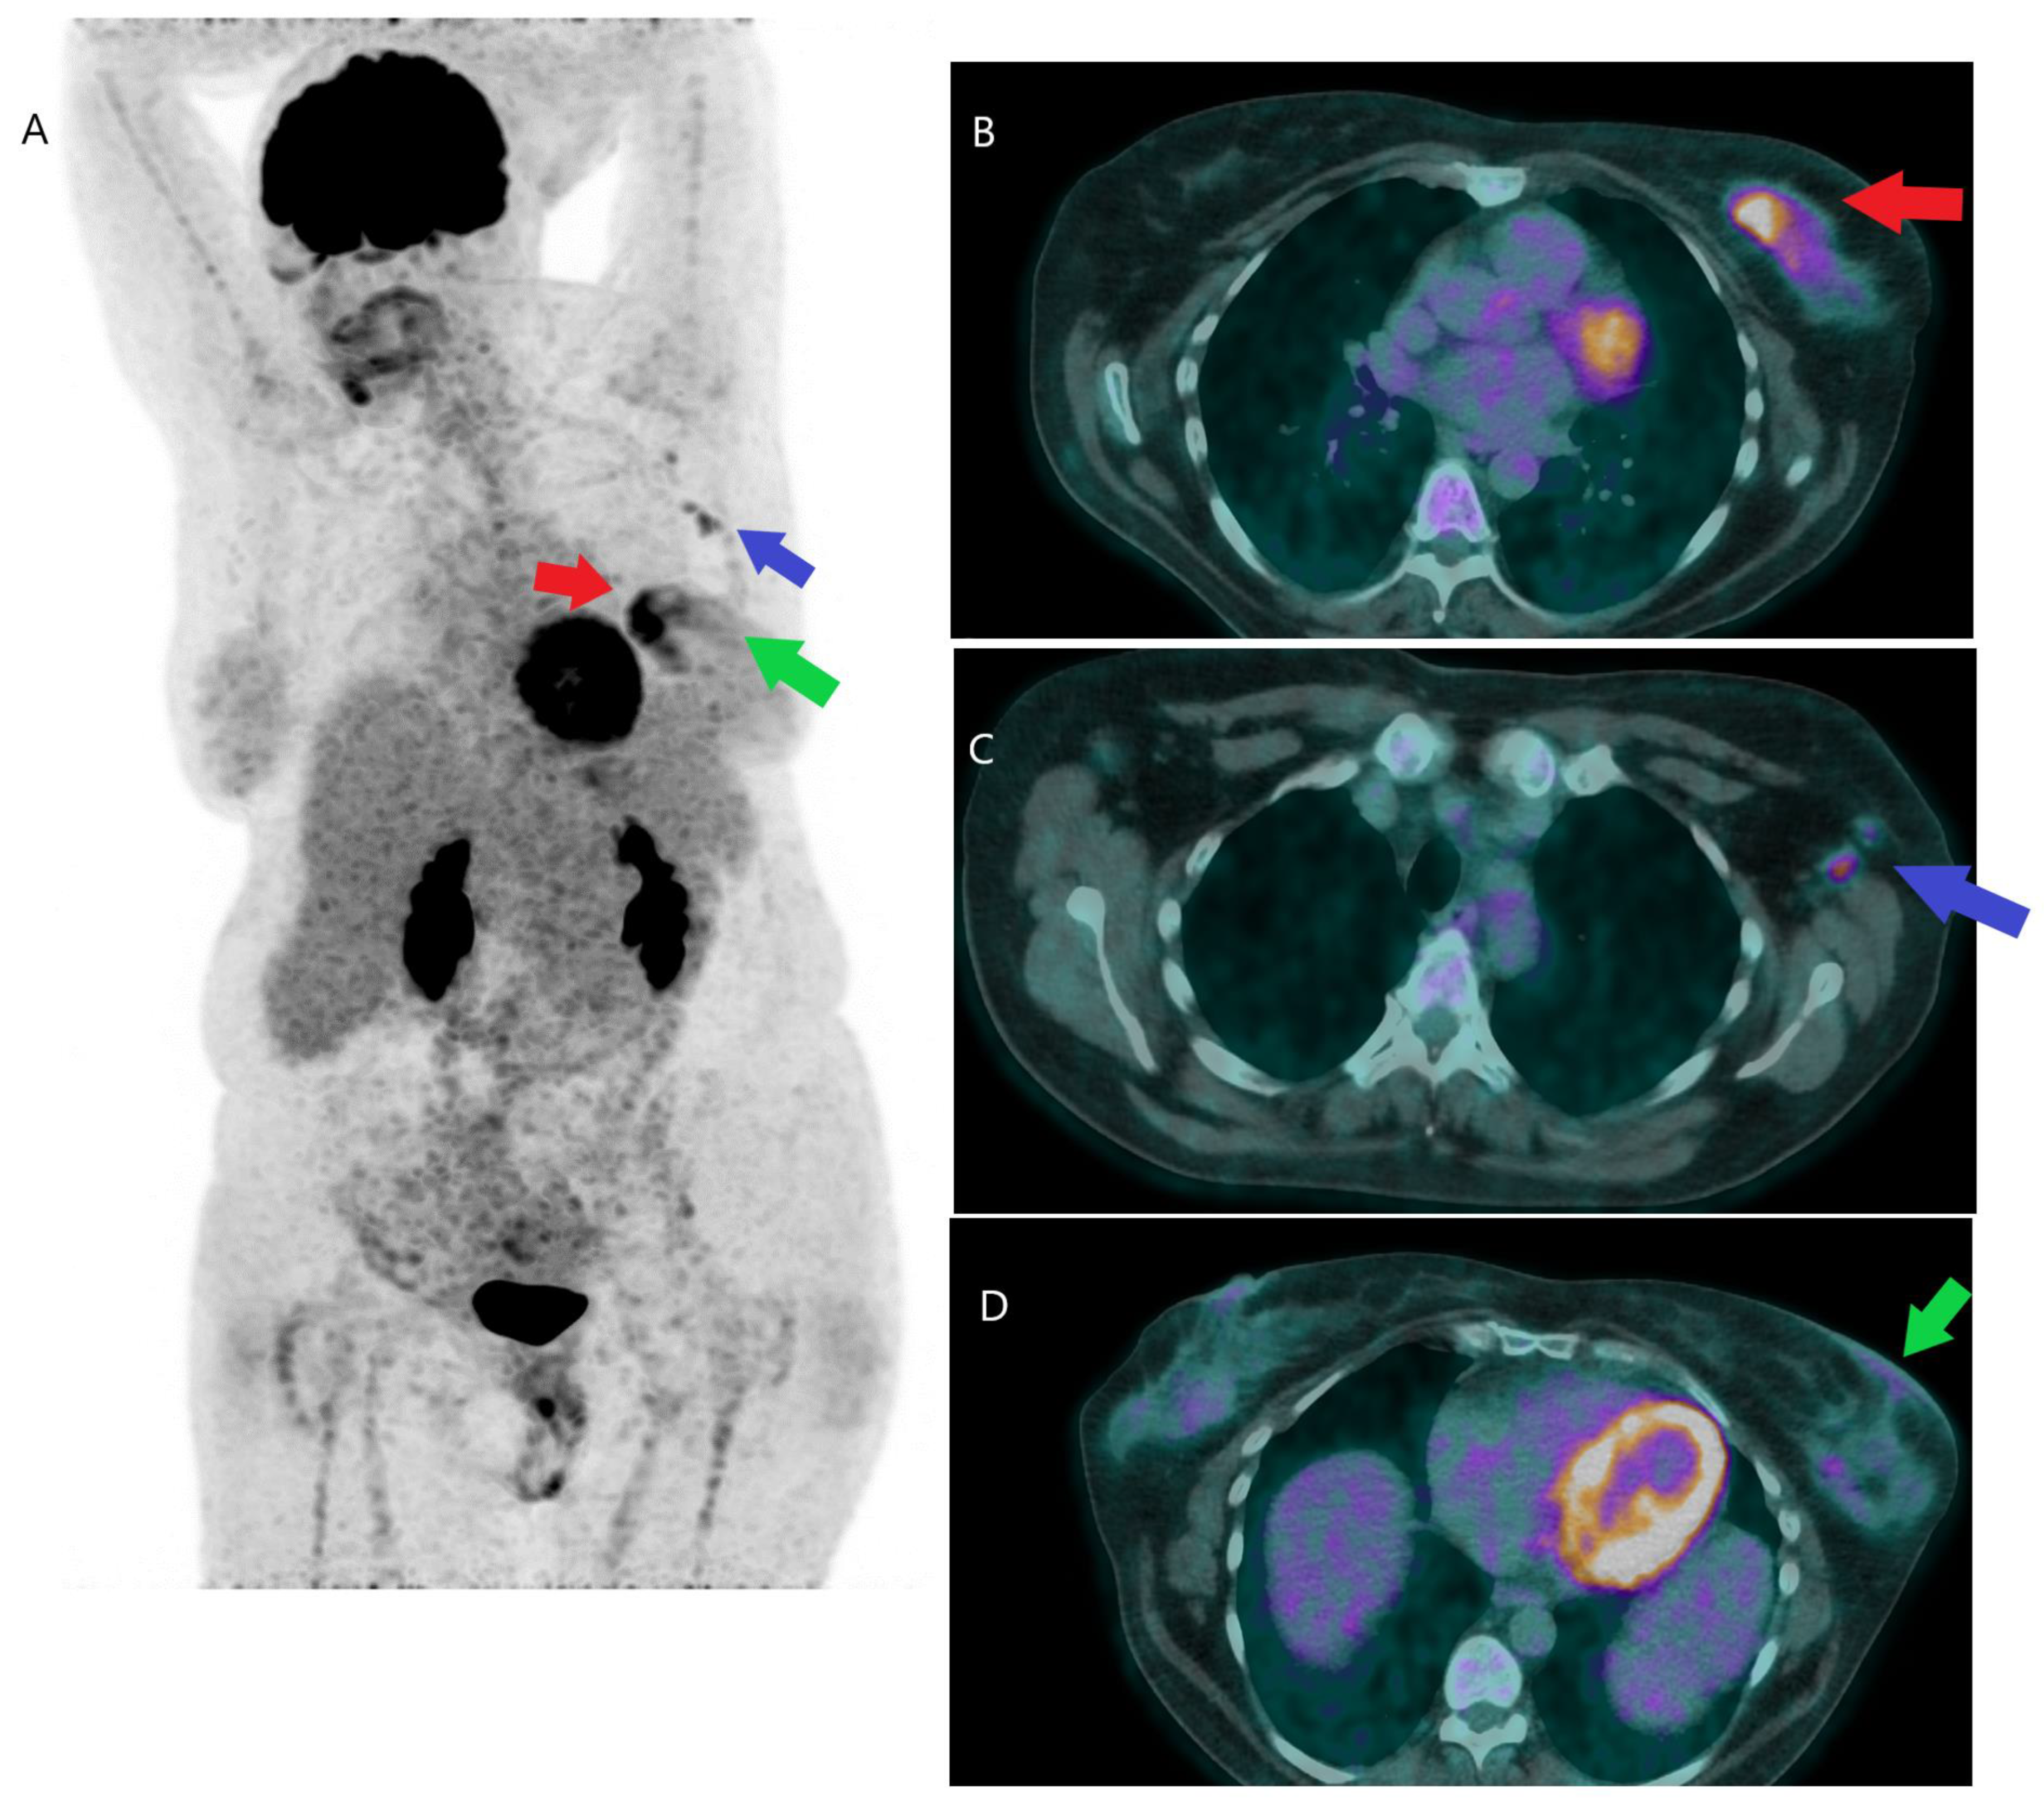

2.1.3. Initial Detection of Distant Metastases

2.2. Recurrent Disease